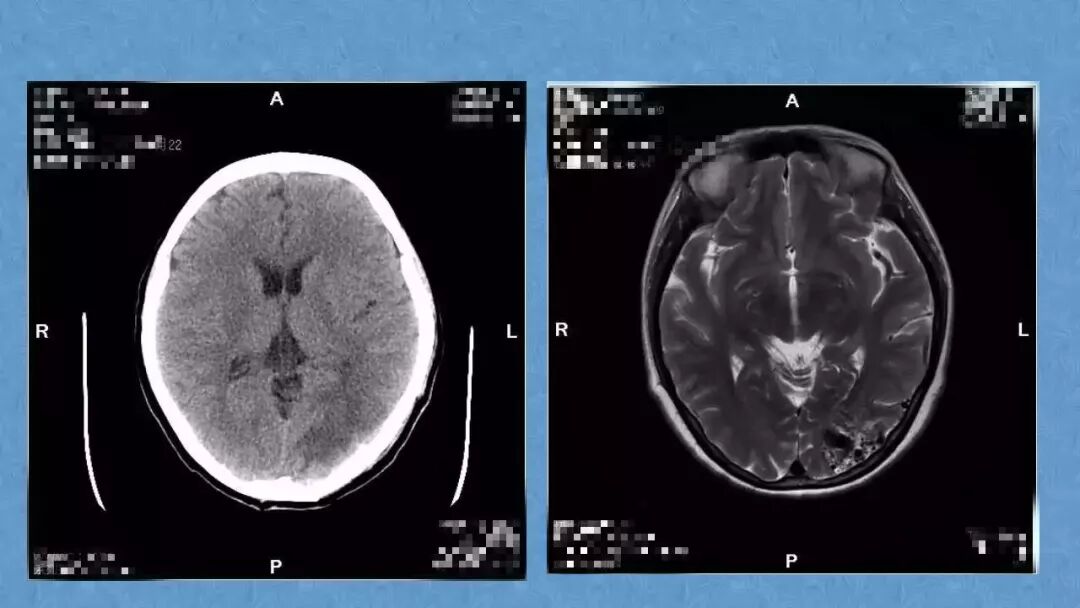

今天为大家分享的是《贝朗时间》第二十九期,湖北十堰市太和医院神经外科张力教授团队带来的:一个AVM患者的48小时纪实,欢迎阅读、分享!

张力教授:AVM切除术